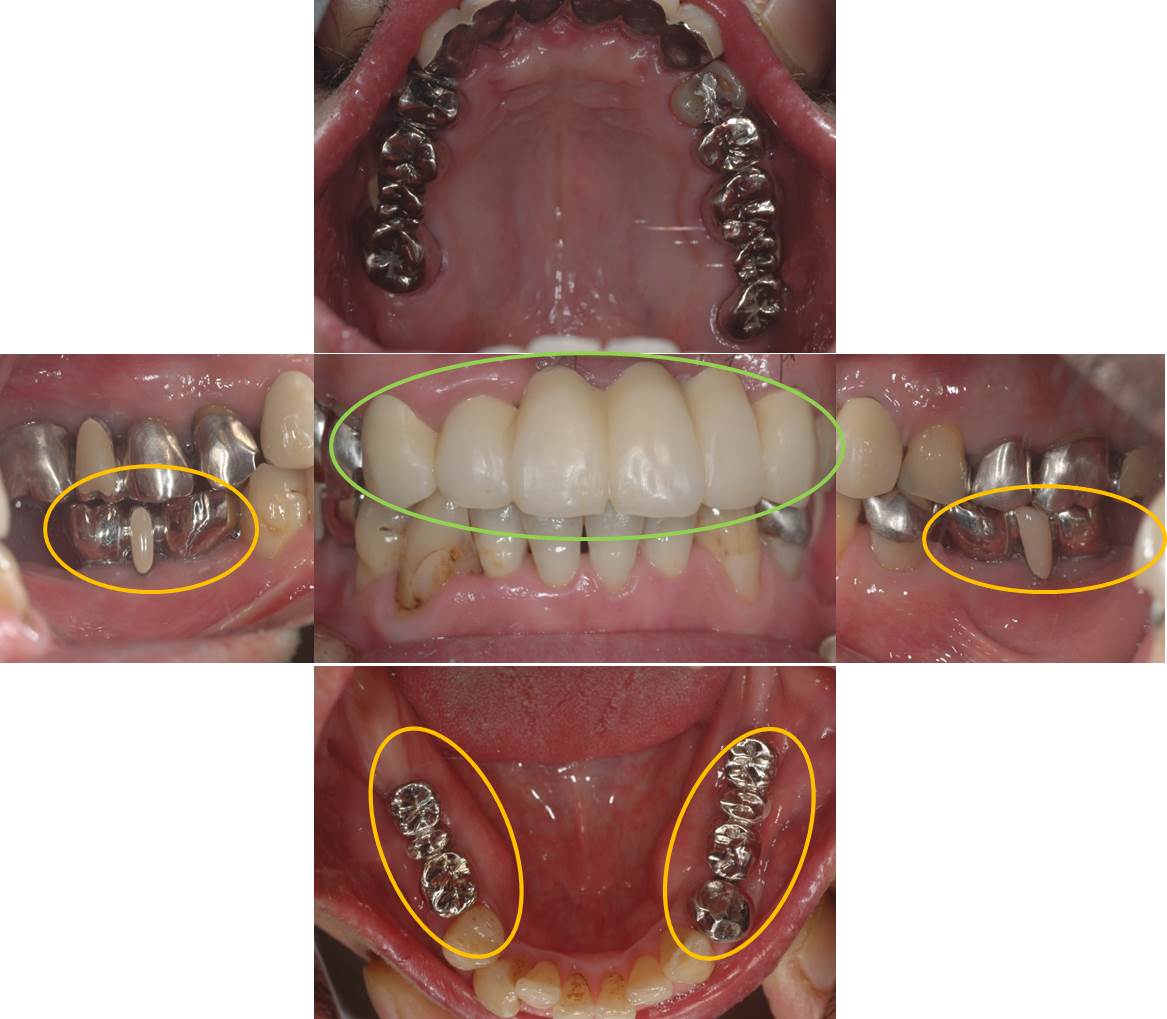

口腔内写真です。

オレンジ○部分の歯が喪失しています。

術後の口腔内写真です。

インプラントの上部構造は金属冠としました。(技工:S.Yonehara)

被せ物はいろいろな補綴装置が選択することができます。色調を気にされる方は、セラミックや硬質レジン(硬質プラスチック)も選択することができます。

色調を気にされない方は壊れにくい金属がお勧めです。